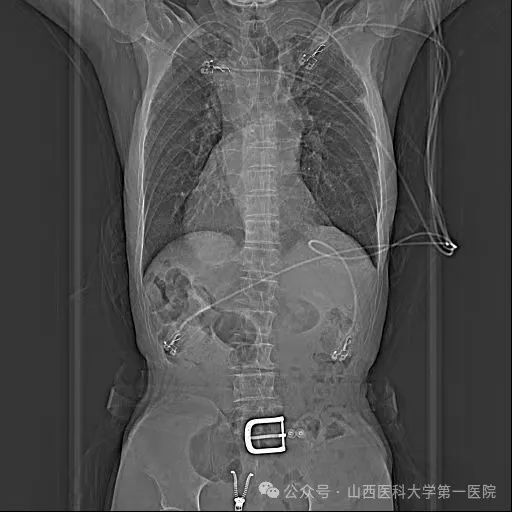

胸片示全内脏反转考虑到患者病情特殊,王睿主任医师带领团队进行了详细的术前讨论,结合患者病史、现有检查资料及技术能力、手术安全性等,与患者及家属充分沟通后,制定了手术方案:在Carto3系统下运用心腔内超声导管(ICE)及X线透视指导射频消融及左心耳封堵手术,并对手术可能出现的风险进行了汇总且制定了相应的防范措施。

老年男性患者1年前因脑梗死住院,完善动态心电图提示持续性心房颤动,建议口服利伐沙班,不规律服药后再次出现脑梗死,因“右位心”经多家医院救治未果来到山医大一院进一步诊治。入院完善检查后发现患者属于真正的右位心,即镜面右位心;CT三维重建显示:心脏解剖结构完全相反,后前位下,左心耳位于最右侧。右位心情况大幅提升了手术难度,尤其在房间隔穿刺时,对心房相对毗邻结构的全部重建、穿刺位点选择,都和常规手术大不相同。